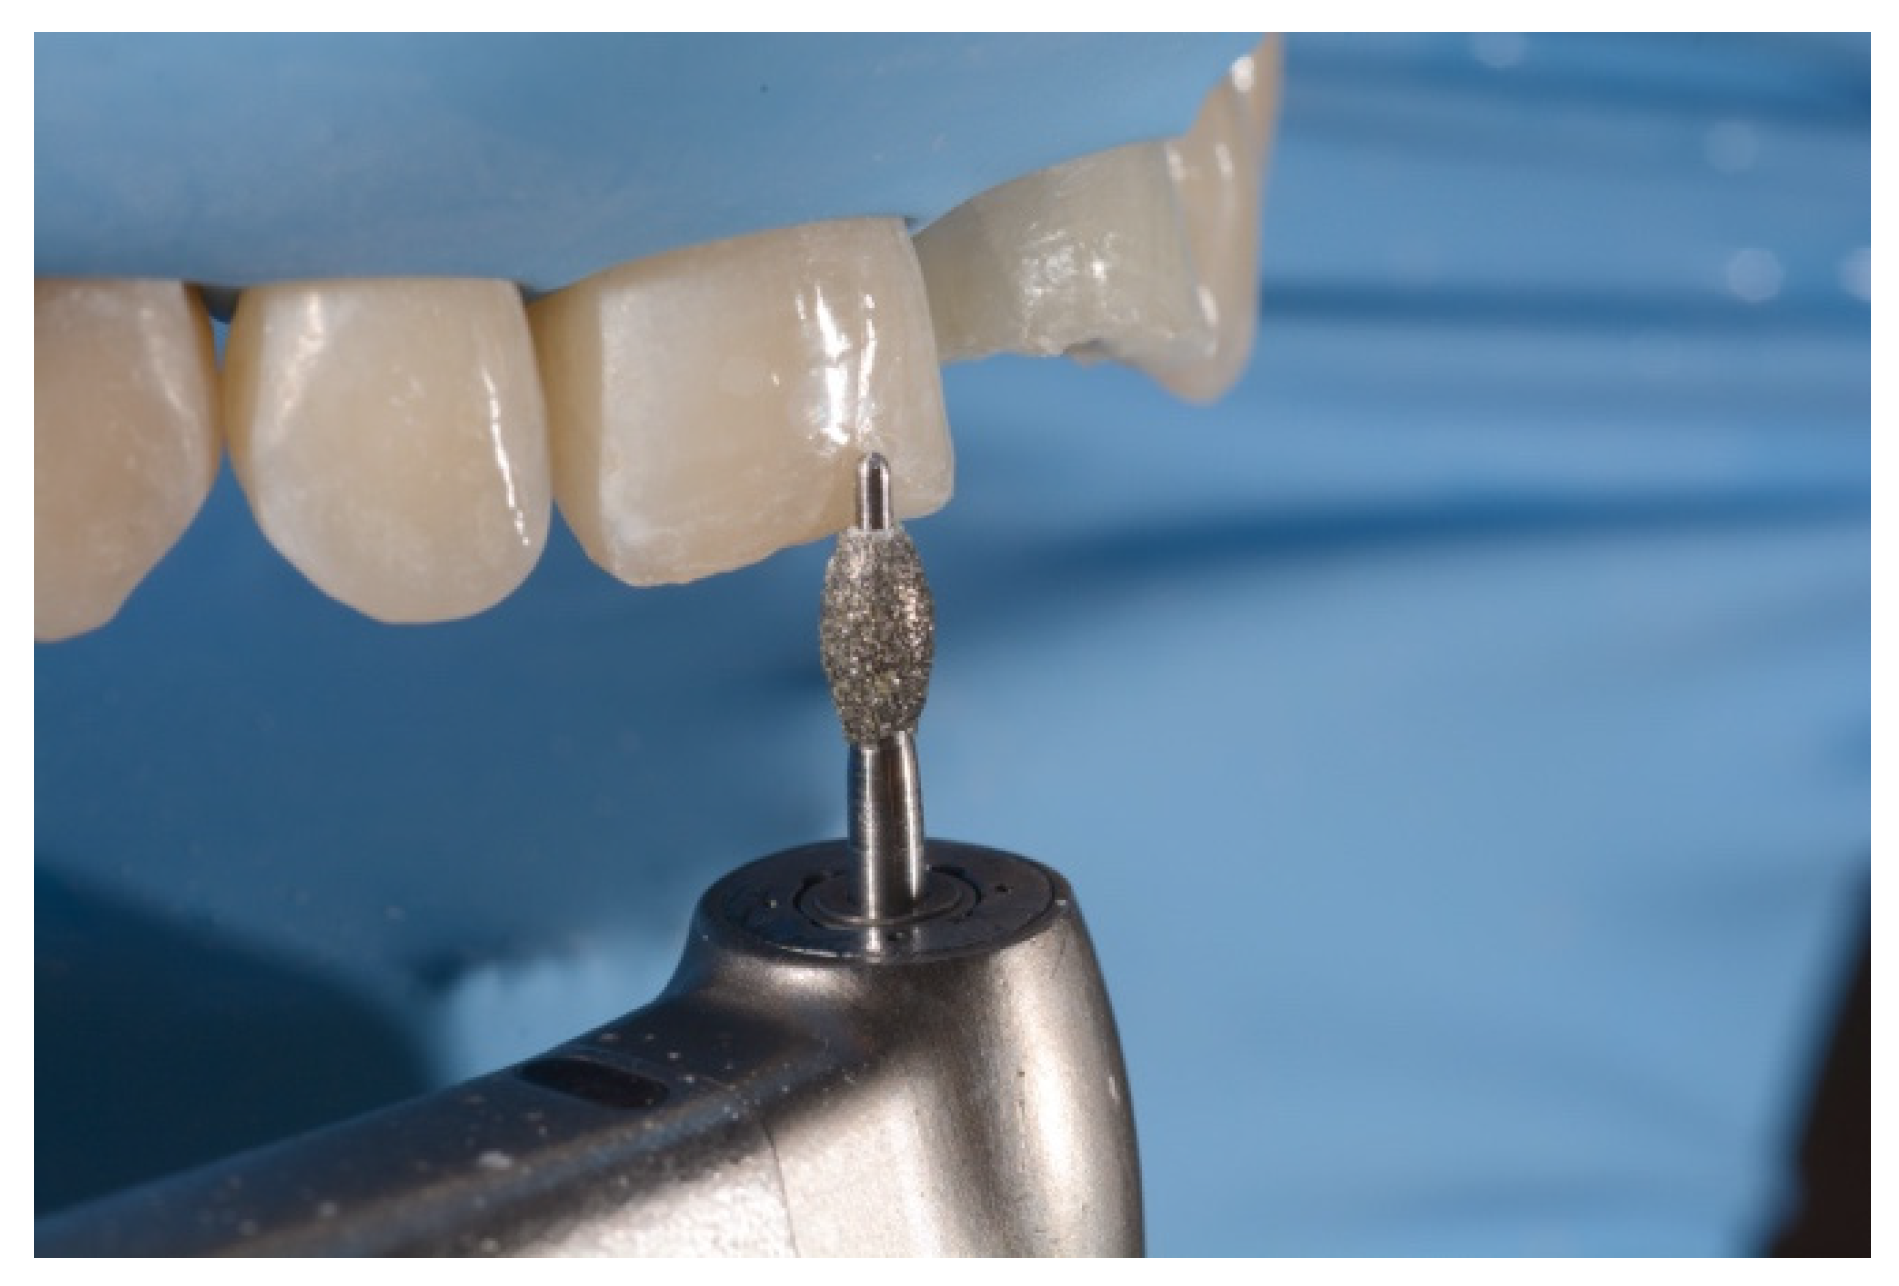

2. Case Presentation